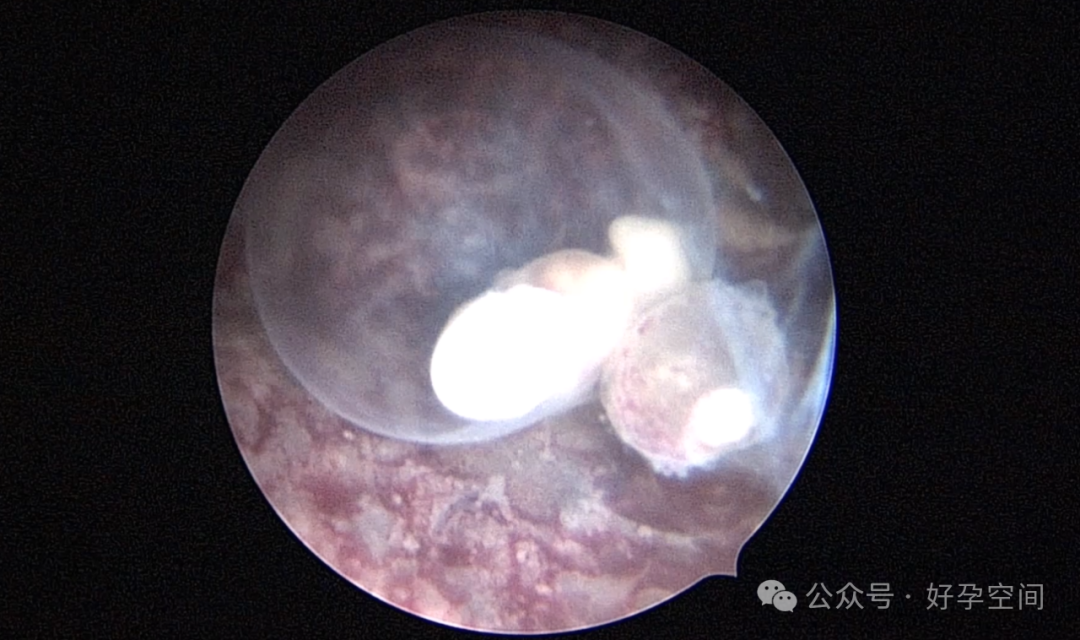

宫腔镜下的胚胎图解

宫腔镜下的胎儿(自妊娠第11周,即受精第9周起称为胎儿)